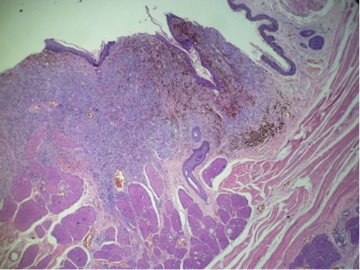

Paciente canino de raza sharpei, macho entero con 09 años de edad. Llega a consulta por una masa perianal. Historias previas de dermatitis, dermatofitosis y melanoma prepucial. Observe con atención las 03 imágenes. Por favor emita su diagnostico marcando una de las opciones que brindamos. Tómese su tiempo y responda!

Figura 1